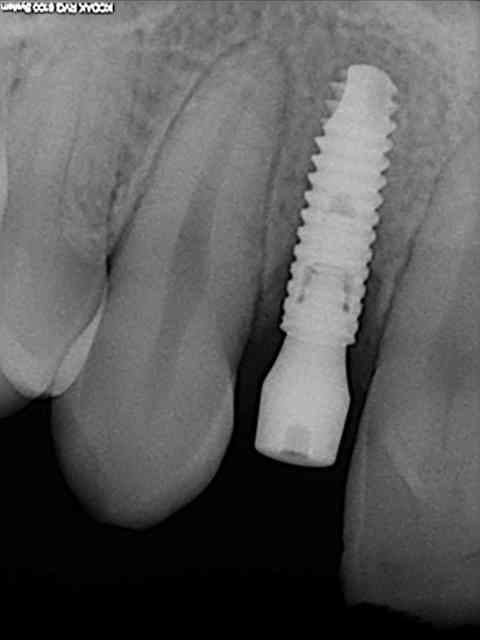

tes implants 12 et 13 n'ont pas le même niveau d'enfouissement, tu n'as pas peur d'une lyse osseuse de 13 pour venir au niveau du col de 12 ?

comment tu fais pour rester en stérile et prendre ton OPT ?